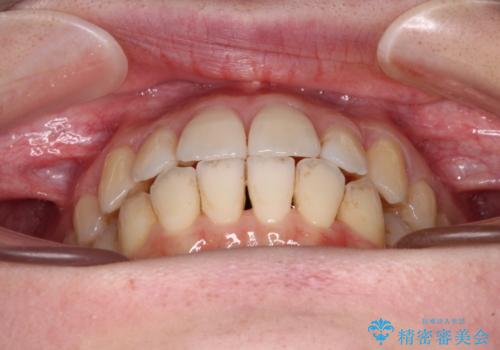

上顎側切歯(上の真ん中から2番目の歯)が舌側転位している場合、インビザラインでは仕上げきれないことが多く、更には無理して動かそうとすると歯髄壊死を起こすリスクが高いと言われています。

インビザラインで歯列を移動する前に、上顎前歯をワイヤー矯正で整え、その後上下歯列をインビザラインにて矯正治療を行うこととしました。

舌側転位している側切歯特有の、切縁の位置が不揃いであったり、根元が内側に引っ込んだ状態であったりという、インビザライン独特の仕上がりになることなく、きれいに整った歯列とすることができました。